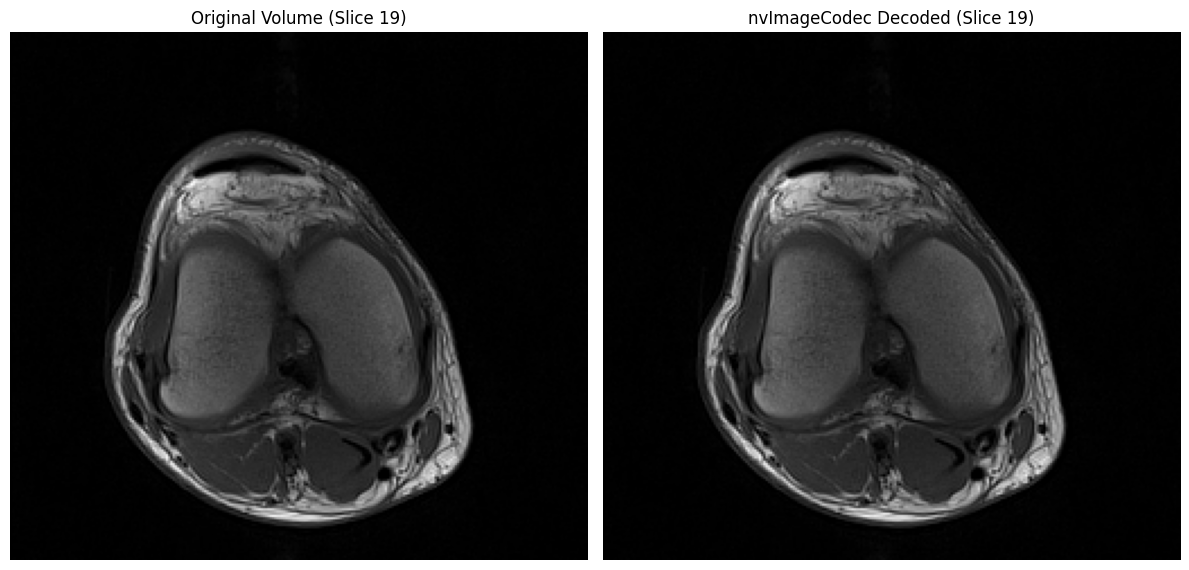

import matplotlib.pyplot as plt

# Visualize a few representative slices from the volume

fig, axes = plt.subplots(2, 3, figsize=(12, 8))

axes = axes.flatten()

# Select 6 evenly spaced slices to display

num_slices = volume.shape[0]

slice_indices = [int(i * num_slices / 7) for i in range(1, 7)]

for idx, ax in enumerate(axes):

slice_idx = slice_indices[idx]

ax.imshow(volume[slice_idx], cmap="gray")

ax.set_title(f"Slice {slice_idx} / {num_slices-1}")

ax.axis("off")

plt.tight_layout()

plt.show()